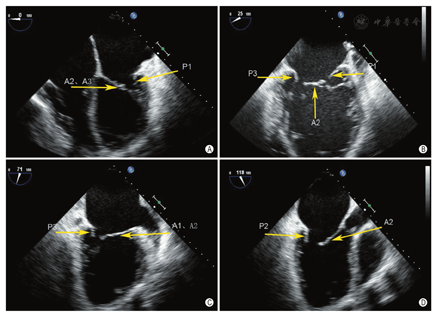

通过采集4个食管中段切面完整显示二尖瓣(图8)。①食管中段的四腔心切面:显示A2、A3和P1;②食管中段的二尖瓣交界处切面:显示A2、P1和P3;③食管中段的二腔心切面:显示A1、A2和P3;④食管中段的长轴切面:显示A2和P2。

MR介入治疗术前和术中,经常使用三维TEE的X-plane双切面(包括二尖瓣交界处二腔心切面及三腔心切面)来评估二尖瓣解剖:二尖瓣交界处二腔心切面能清晰显示二尖瓣后叶P1及P3、前叶A2,而三腔心切面能清晰显示二尖瓣前叶A2、后叶P2。也可通过二尖瓣的"三维外科视野"立体显示二尖瓣前后叶(图9)。

二维、三维TEE通过上述切面评价MR的机制、程度以及部位,并确定瓣膜运动异常的扇区。